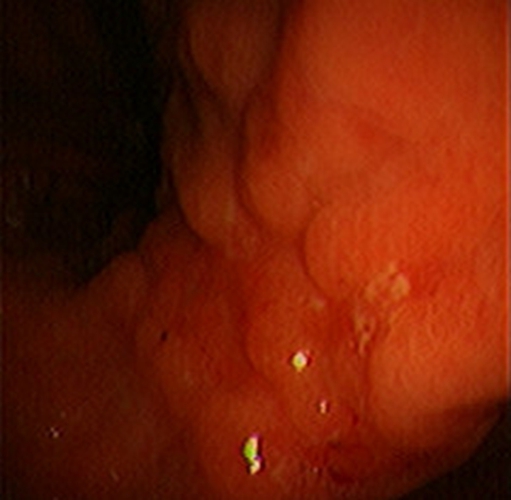

急性胃炎圖片

急性胃炎陽性表現

急性胃炎陽性的表現的

急性胃炎陽性的表現